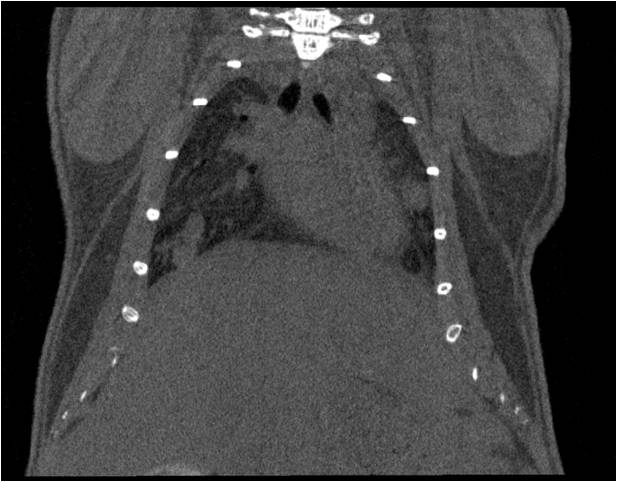

肺轉移

小鼠模式,22.5μm像素

正常

8天 14天

無造影劑注入 造影劑注入